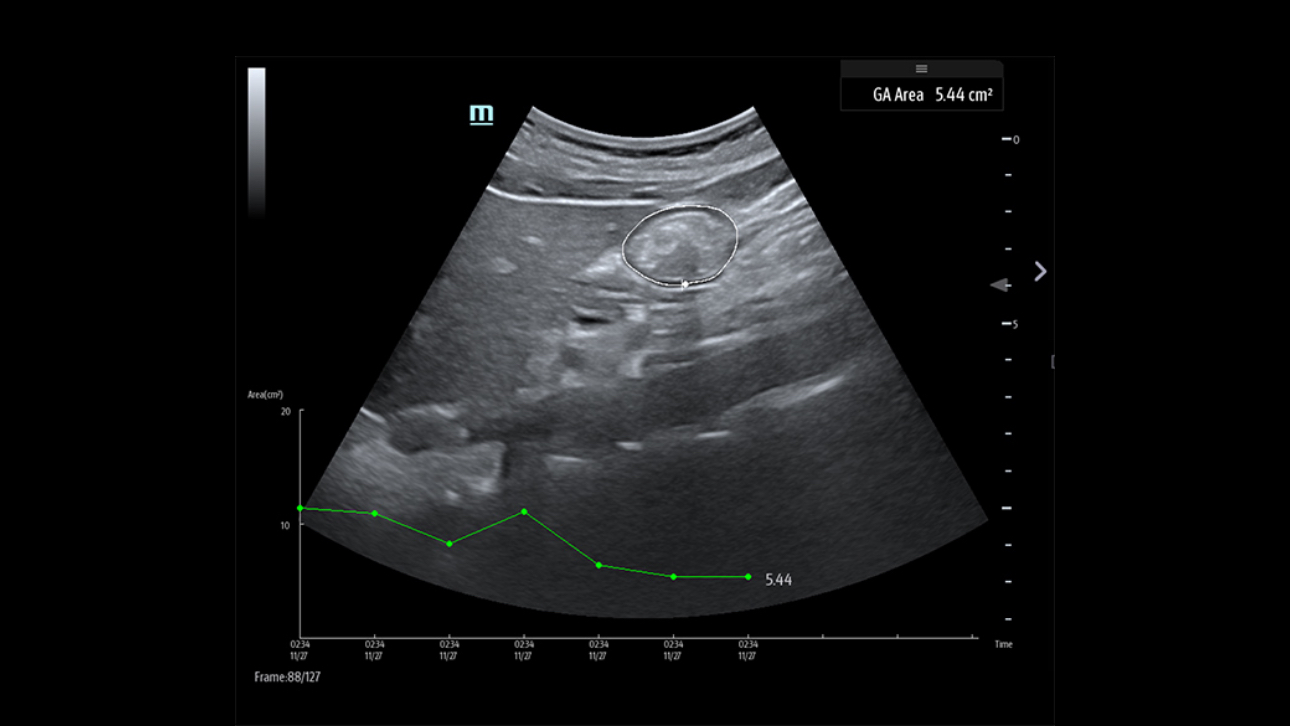

L'├®chographe TE9 a ├®t├® con?u pour faciliter les soins et ├®tendre les capacit├®s d'imagerie pour lŌĆÖanesth├®sie, les urgences et les soins intensifs. Gr?ce ├Ā ses fonctions avanc├®es, son grand ├®cran tactile et sa technologie d'imagerie sup├®rieure, l'├®chographe TE9 permet d'am├®liorer l'efficacit├® clinique et dŌĆÖassurer un diagnostic en toute confiance. Gr?ce ├Ā des outils dŌĆÖacquisition et de calculs automatiques, les soignants peuvent obtenir des mesures rapides et reproductibles dans le cadre d'examens et proc├®dures fiables, m├¬me dans des environnements o├╣ le rythme est soutenu.